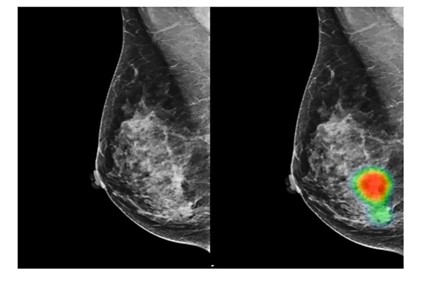

- Finding Breast Cancer: A South Korean study found that an AI-based tool achieved 90% sensitivity in detecting breast cancer with mass, outperforming radiologists who achieved 78%. The same system also demonstrated superior capabilities in early breast cancer detection with 91% accuracy compared to radiologists at 74%.

The system is designed to learn when to rely on the AI’s prediction and when to “defer to a clinician.” In one test scenario using a large mammography dataset, this collaborative approach reduced the number of false positives by 25% compared to standard clinical workflows, all without missing any true positive cases. This ensures that the final decision is always made using the best of both worlds.